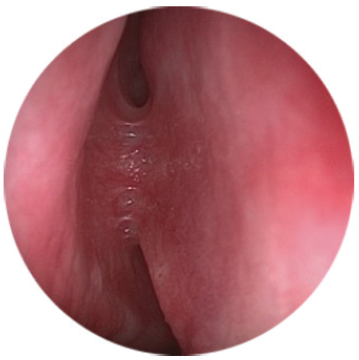

The study included patients with complaints of long-term lacrimation and suppuration (more than 6 months). The patients were diagnosed and treated at various institutions – at otorhinolaryngological and ophthalmological departments of the Pirogov State clinical hospital (Moscow) and hospitals of the MEDSI group of companies (Moscow) with the established diagnosis of “chronic dacryocystitis” during the period from 2015 to 2019. The clinical examination of patients included disease history, biomicroscopy of the anterior segment with evaluation of the eyelids, and anterior rhinoscopy. Endoscopic examination of the nasal cavity was performed using rigid endoscopes of 0° and 30° and 4 mm in diameter, after local application anesthesia with 10% lidocaine hydrochloride solution, with examination of all the endonasal structures of the nasal cavity: inferior nasal meatus, nasal floor, inferior nasal concha, middle nasal meatus, osteomeatal complex, area of the hamate bone, front end of the middle turbinate, and lacrimal tubercle of the nasal septum (Fig. 1–3).

Fig. 1. Endoscopy of the nasal cavity. Endoscope 4 mm 0°. The lacrimal tubercle covers the area of projection of the lacrimal sac